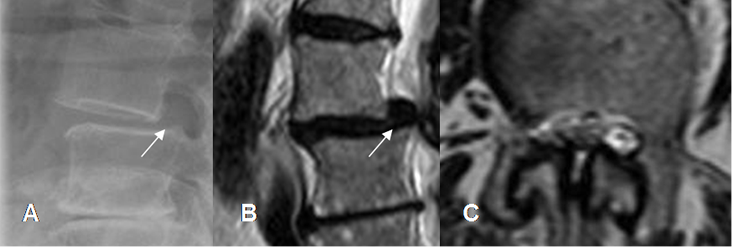

Fig 55. Canal estrecho por anterolistesis.

A: Rx lateral y B: RM sagital en T2. Anterolistesis G I de L3, sobre L4.

C: RM axial en T2. Presencia de canal estrecho mixto asociado.